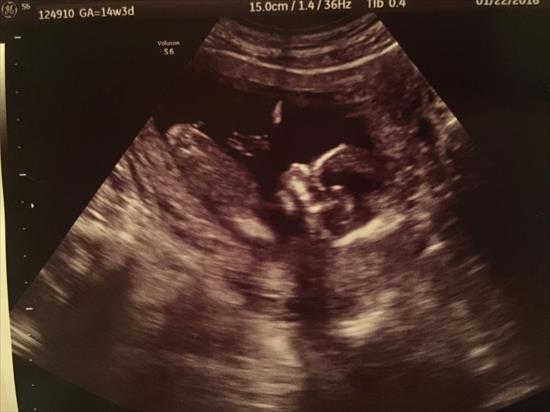

Of course at 14w 3d they can't give 100% on the gender, but they guessed girl. I'm not 100% convinced, so I thought I'd ask for your opinions! :)Attachment 29648Attachment 29649

I would not personally feel confident that was a girl. But I do get a girly vibe from the 2nd pic for some reason.